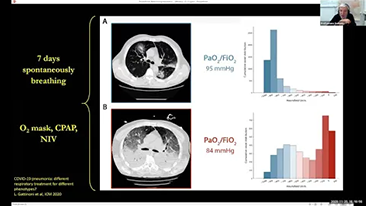

Choosing the correct ventilator settings for treating patients with respiratory tract disease is an important issue. Since the task of specifying the parameters of ventilation equipment is entirely carried out by a physician, their knowledge and experience in the selection of these settings has a direct effect on the accuracy of their decisions. There are numerous ventilation modes and decision-supporting tools which have been developed specifically to help caregivers improve efficiency and eliminate errors in clinical decision-making.